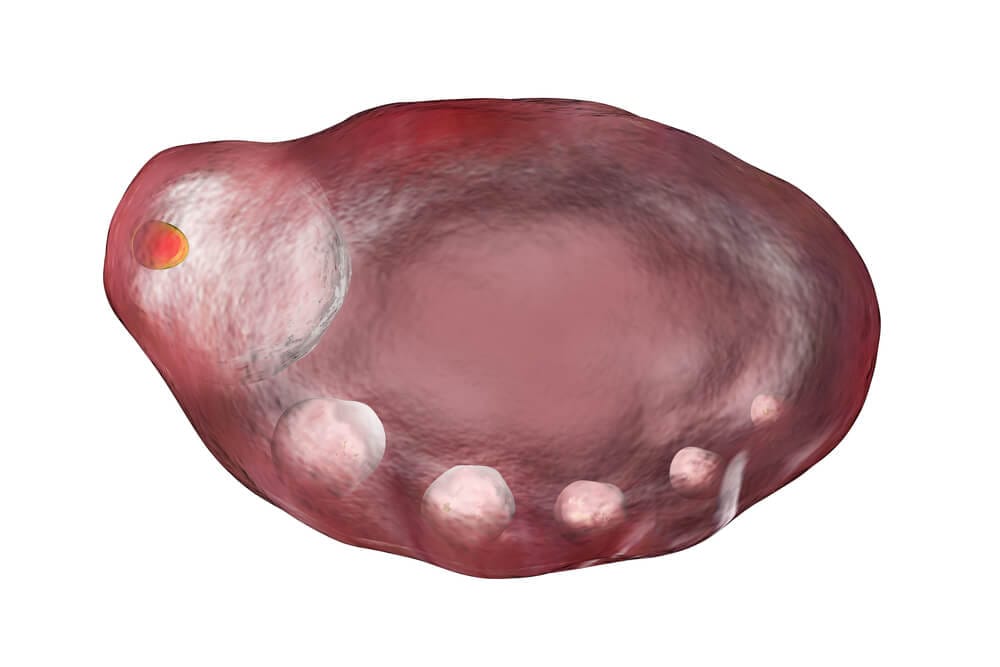

A síndrome dos ovários policísticos, também conhecida como SOP, é uma doença caracterizada pela presença de múltiplos microcistos nos ovários, resultando em distúrbios hormonais que podem afetar a autoestima e a fertilidade da paciente.

Por ser uma doença multifatorial, o diagnóstico de SOP inclui uma análise aprofundada para determinar se o quadro clínico trata-se de um cisto no ovário ou da síndrome dos ovários micropolicísticos, condições que se diferenciam ao comparar o tamanho e a quantidade de microcistos, além de um conjunto de sinais e sintomas.

Ultrassom transvaginal

Esse exame de imagem corrobora com o diagnóstico de SOP e deve ser considerado juntamente com o quadro geral da paciente, já que a visualização de microcistos nos ovários não significa que a mulher sofra com os sintomas desse problema (a paciente apresentar ovário micropolicístico pelo ultrassom não indica necessariamente que ela seja portadora da síndrome dos ovários micropolicísticos).

- Identificação de ao menos 12 microcistos no ovário com tamanho entre 2 a 9 mm e/ou volume ovariano superior a 10 cm³ (desde que não contenha cisto acima de 10 mm ou tumor ovariano).